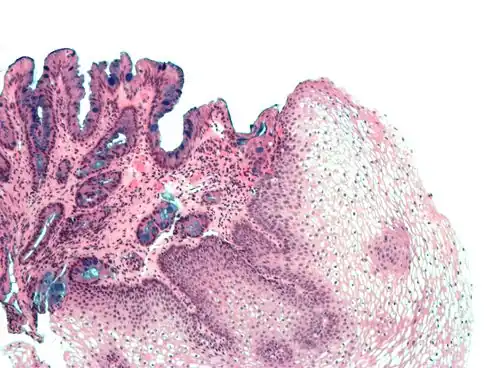

| Tinción hematoxilina-eosina | Bicomponente Anfifílica |

|

Tinción histológica general |

| Tinción hemalumbre-eosina | Similar a la tinción H&E con colores más marcados y definidos | Tinción histológica general |

| |